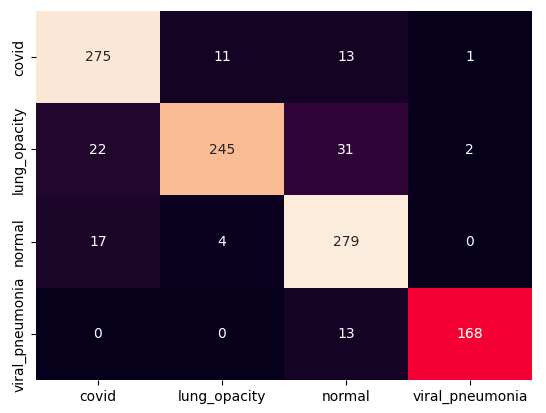

III.2 Classification results

The training procedure in all scenarios has converged. Looking at the evolution of training and validation accuracy (Fig. 11a) indicates that a larger validation dataset would be beneficial. To stabilise the classifier training a procedure of multiple training runs to select the best model is used (Materials and methods). Resulting classifiers are able to discriminate between classes with good precision, for example, see the confusion matrix of the best overall model presented in Fig. 11b. It can also be seen that for the normal class, the rate of misclassified images as COVID-19 ones is higher than for other classes. This effect is present for all models although smaller for the ones based on the EfficientNet-B0 architecture. In addition, the EfficientNet-B0 variants excel if the correct classification of viral pneumonia class images with the smallest rate of errors. However, the EfficientNet-B0 GAN augmentation scenario shows increased misclassification of healthy images which leads to a poor performance. The evolution of the training accuracy as well as confusion matrices for all models are summarised at the end of this section.

The results of the best-trained model for each of the four scenarios are analysed using a number of popular metrics. As presented in Table 2 the most accurate model, based on multiple metrics, is an EfficientNet-B0 trained on the balanced dataset. Obtained accuracy of is in line with results obtained by Khan E. et al. Khan et al. (2022) i.e. accuracy using classical augmentation and standard transfer learning with EfficientNet-B1 or accuracy with a modified approach.

Training results for the two architectures are summarised in Figs. 13, 14, 15, 16, and Table 3. For each architecture four scenarios are considered as described in Training process part of the Materials and methods Section.